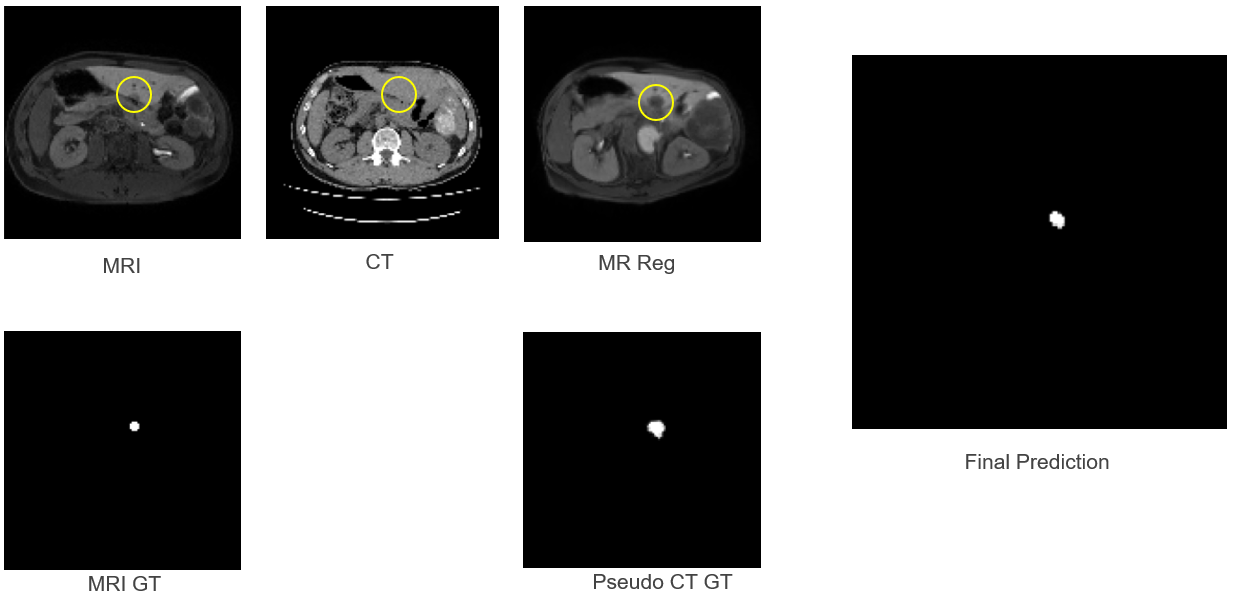

3.6 Qualitative Analysis

Figure 5 illustrates the pipeline stages for clinical data and encapsulates the central finding of this research. The tumour is clearly visible in the MRI and MR_Reg images, highlighted by the annotation. Critically, the corresponding region in the CT image shows no visible tumour; the pathology is genuinely invisible in this modality.

The Pseudo CT_GT, generated by warping the MRI ground truth through the learned registration, correctly indicates the tumour location. The final prediction produces a segmentation that approximately identifies the tumour region but fails to capture the precise shape and extent. This observation is significant: the framework achieves localisation (finding the approximate tumour centre) even when precise segmentation (accurate boundary delineation) is not achievable. Whilst the Dice score is low due to the shape mismatch, the centre-point of the prediction falls within the true tumour margin, verifying successful localisation.

Whilst boundary delineation (Dice) was compromised by feature absence, the framework successfully recovered the tumour locus. The topological overlap is low, but the semantic localisation is preserved. This indicates that the registration successfully transferred the ‘region of interest’, even if the segmentation network could not refine the margins due to the lack of contrast. These findings demonstrate that spatial priors (registration) are insufficient without appearance cues (segmentation features) for precise boundary recovery, yet remain valuable for approximate tumour localisation.

For clinical applications such as surgical planning, localisation may provide meaningful value even when Dice scores are low. The Dice coefficient penalises boundary errors heavily, but for needle placement in ablation procedures, identifying the tumour centre with reasonable accuracy may be more clinically relevant than perfect boundary delineation.

Refer to caption

Figure 5: Clinical Data Results: The tumour is visible in MRI (highlighted) but invisible in the corresponding CT region. The final prediction approximately localises the tumour despite poor Dice score.